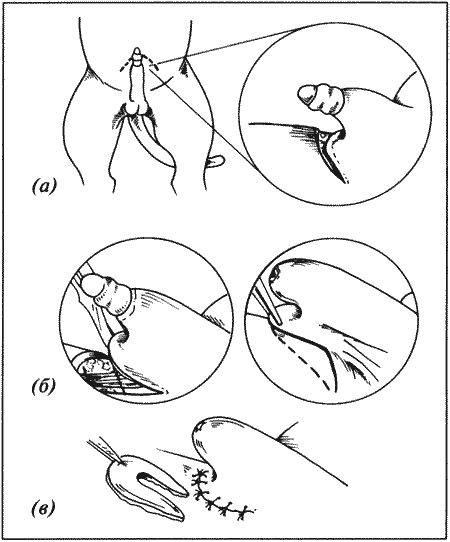

Рассматриваются следующие вопросы: нормальная физиология собак и кошек; болезни репродуктивной системы; бесплодие самок и бесплодие самцов; нормальное функционирование и дисфункция молочных желез; спаривание; искусственное осеменение; протекание беременности и роды; уход за новорожденными щенками и котятами, их наследственные и инфекционные болезни; техника оперативных вмешательств на репродуктивных органах; фармакологический контроль репродукции.

В Руководстве приводится обзор нормальной физиологии и эндокринологии размножения собак и кошек, рассматриваются причины бесплодия самок, функция и дисфункция молочных желез, нарушения, возникающие у небеременных самок, а затем столь же подробно описываются соответствующие проблемы у самцов. Далее обсуждаются вопросы спаривания и искусственного осеменения, а также протекание беременности и родов. Специальный раздел посвящен наблюдению и лечению новорожденных щенков и котят; он включает обзорные данные по наследственным порокам, обсуждение роли инфекционных болезней и мер по их предупреждению. В заключительных главах книги рассматриваются терапевтические и хирургические методы, применяемые для коррекции репродуктивных нарушений.